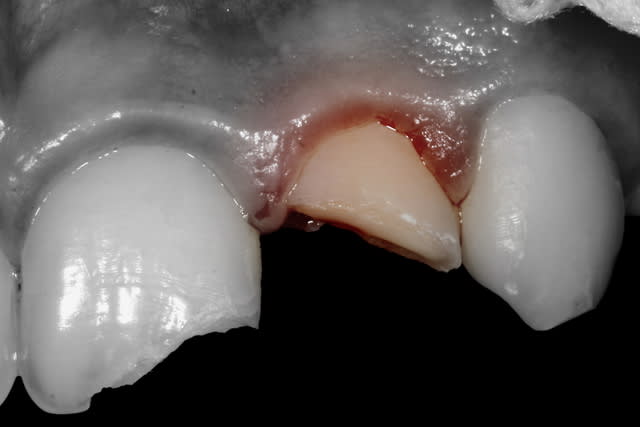

- 22 présente une exposition pulpaire ancienne de 20 heures. 20 heures donc que les germes buccaux contaminent directement la pulpe, heureusement jeune et donc avec un fort potentiel de défense.

Une pulpotomie partielle est réalisée afin d'éliminer le tissu le plus contaminé. De la Biodentine est utilisée ; son avantage par rapport au MTA est de ne pas noircir. Du CaOH aurait un taux de succès moindre.

Sur la photo4, celle apres la pulpo partielle je suppose, as tu eu une hémostase naturelle ? As tu directement posé le MTA ? La pulpe semble assez "rouge foncé"

- L'éviction du tissu pulpaire est réalisée avec une fraise-boule acier sur contre-angle bague bleue. La fraise est stérile : n'a rien touché d'autre avant.

La quantité de tissu à enlever dépend de l'ancienneté de l'exposition. C'est "empirique" : on imagine la profondeur de tissu infecté depuis l'exposition. 1 mm si le trauma a quelques heures, toute la pulpe camérale si 24h, toute la pulpe si plus de 48-72h.

- L'hémostase est faite avec un coton stérile (des boulettes de coton dans un sachet passé à l'autoclave).